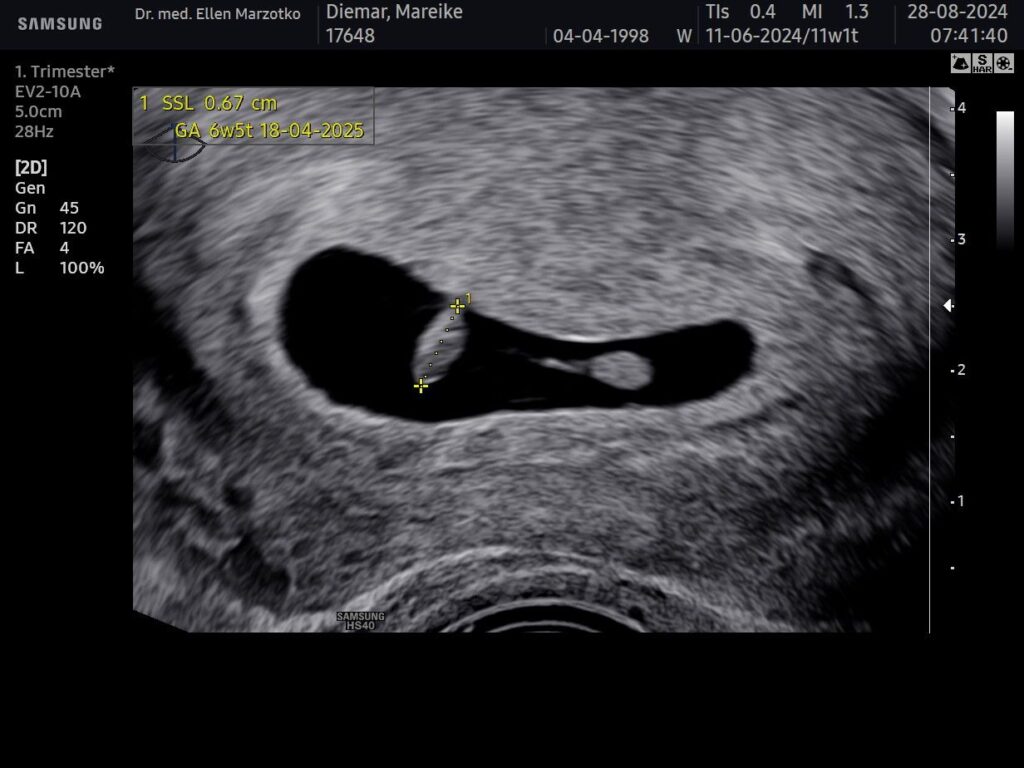

An diesem Tag waren wir in der 7. SSW (6+6). Das bist du, als wir dich das erste Mal gesehen haben: